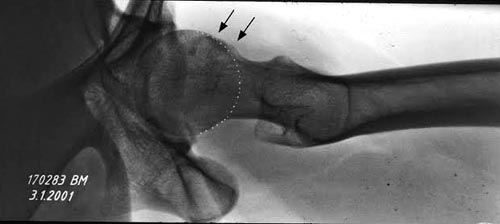

Здесь представлены рентген, боковой, МРТ и клинические снимки

деламинации хряща одного того же пациента.

Имя     : False Profile.jpg

Тип     : image/jpeg

Размер  : 63587 байтов

Описание: отсутствует

Url     : http://weborto.net:8080/pipermail/ortho/attachments/20160418/78e1d55d/attachment-0006.jpg